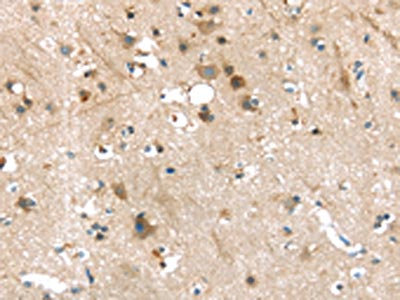

The image on the left is immunohistochemistry of paraffin-embedded Human brain tissue using CSB-PA576176(P2RY2 Antibody) at dilution 1/30, on the right is treated with synthetic peptide. (Original magnification: ×200)